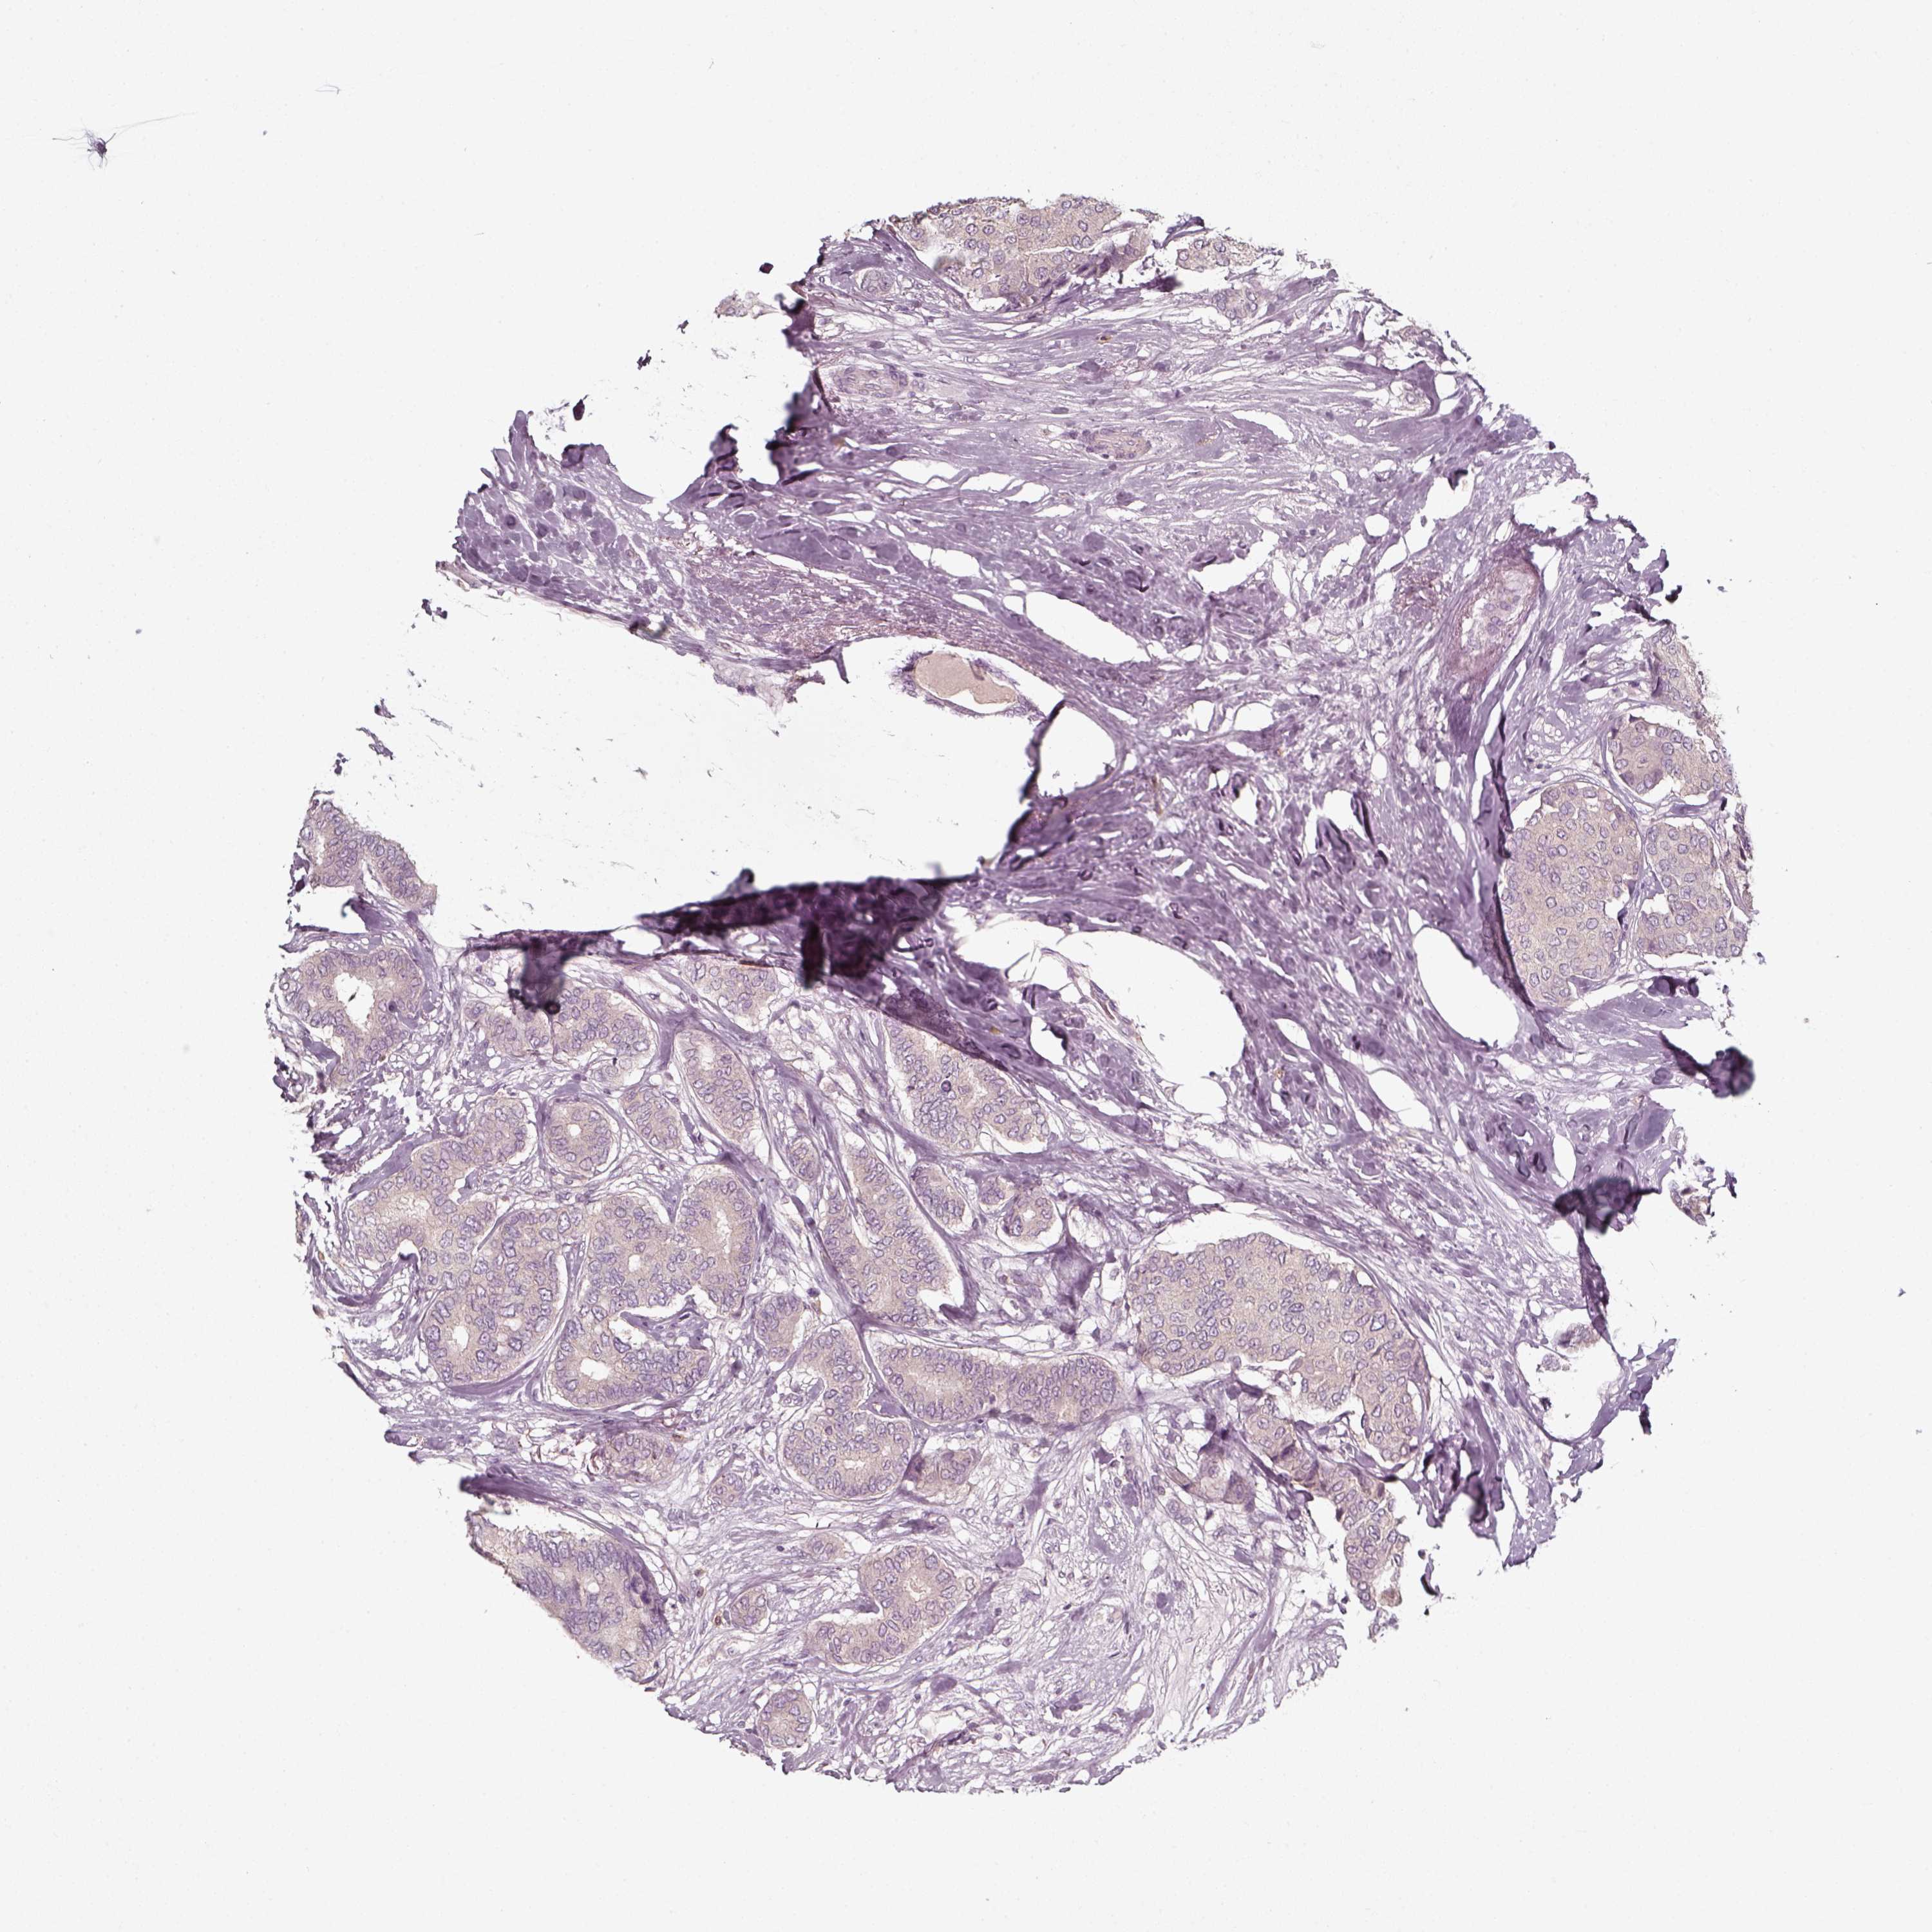

CANCER BREAST CANCER Show tissue menu

BRCA TCGA BRCA VALIDATION PROTEIN EXPRESSION